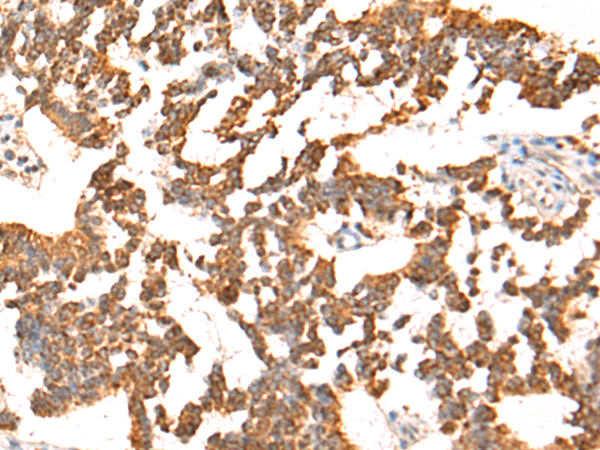

IHC positive control: |

Human colorectal cancer and Human liver cancer |

IHC Recommend dilution: |

50-200 |